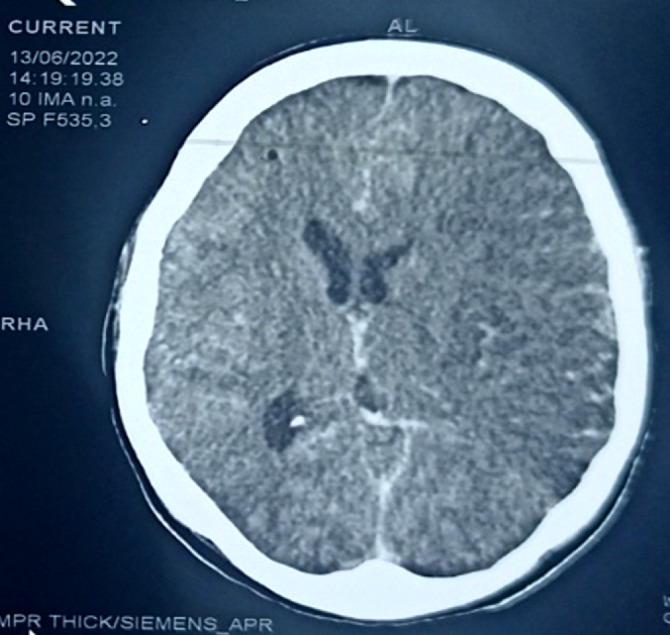

Extended-spectrum beta-lactamase-secreting Enterobacteriaceae (ESBL-E) infections constitute a real global public health problem, particularly in sub-Saharan Africa. We report here two cases of ESBL-E meningoencephalitis in young female patients occurring in a gestational context observed at the infectious and tropical diseases department of the Point G university hospital in Bamako. The first woman, who recently had an abortion, was being treated with ceftriaxone when she was admitted for meningeal syndrome and pyramidal syndrome associated with brain damage. Escherichia coli resistant to penicillins and cephalosporins was isolated from cerebrospinal fluid (CSF), blood and a purulent genital swab. She recovered under meropenem treatment for 21 days, with few sequelae.The second had given birth in the weeks prior to the onset of generalized infection. She was admitted for meningeal syndrome and pyramidal syndrome associated with several cerebral lesions disclosed by the CT scan. Multidrug-resistant E. coli was isolated from CSF and genital purulent sample. She recovered (with sequelae) under treatment with meropenem for 21 days. These two observations show that female genital infections (postpartum or post abortum) with E. coli can cause forms as serious as meningoencephalitis, in addition to the abortion they cause. ESBL-E -producing strains may be involved and represent a major therapeutic challenge. Better infection prevention and control would prevent multi-drug-resistant infections and their spread. Regulating the use of carbapenems and other antibiotics still effective against multi-resistant bacterial strains within the framework of global health (one health) would avert an incurable pandemic of highly resistant and emerging bacteria (HRB).